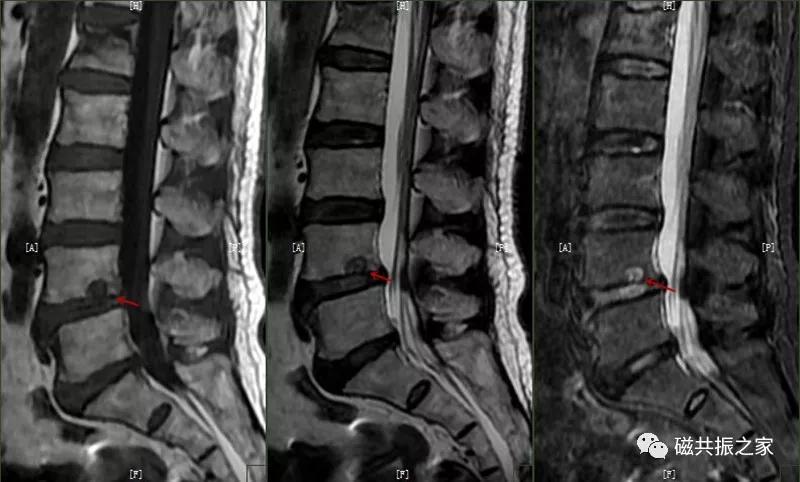

矢状面显示椎体上或下椎间盘面异常信号,常呈长T,长T2信号,见髓核信号突入椎体内,常伴椎间隙变窄,常见于L3~S1椎体。

椎体边缘骨,类似于Schmorl改变,一类是椎体生长板和椎体二次骨化中心软骨发育异常,致其不能完全愈合,造成的椎间盘疝入其间,形成边缘体的椎体边缘骨。

椎体生长板和椎体二次骨化中心软骨发育异常,致其不能完全愈合,造成的椎间盘疝入其间,形成边缘体的椎体边缘骨。

另一类是椎体后缘骨内软骨结节,椎间盘疝入骨内,形成椎体后缘的Schmorl结节样改变,椎体终板及髓核等突入其中,椎体骨质增生,常见于L4、L5椎体下缘。

椎体后缘骨内软骨结节,椎间盘疝入骨内,形成椎体后缘的Schmorl结节样改变,椎体终板及髓核等突入其中,椎体骨质增生,常见于L4、L5椎体下缘。